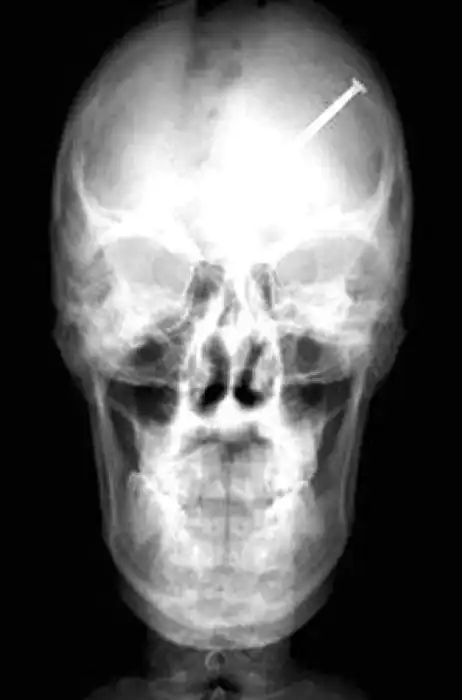

Необычные предметы в теле людей на рентгеновских снимках

На рентгеновских снимках людей порой можно обнаружить самые необычные предметы, которые находятся в их теле.